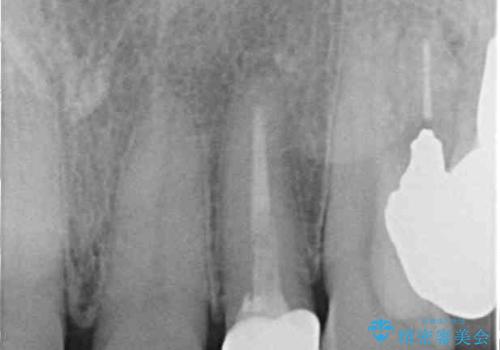

- 前歯の根管治療の際に、一時的に見た目を回復したままの状態で放置してしまったとのことで来院された患者様です。

土台の状態は良好であったため、仮歯に置き換えた上でオールセラミッククラウンにて補綴治療を行うこととしました。